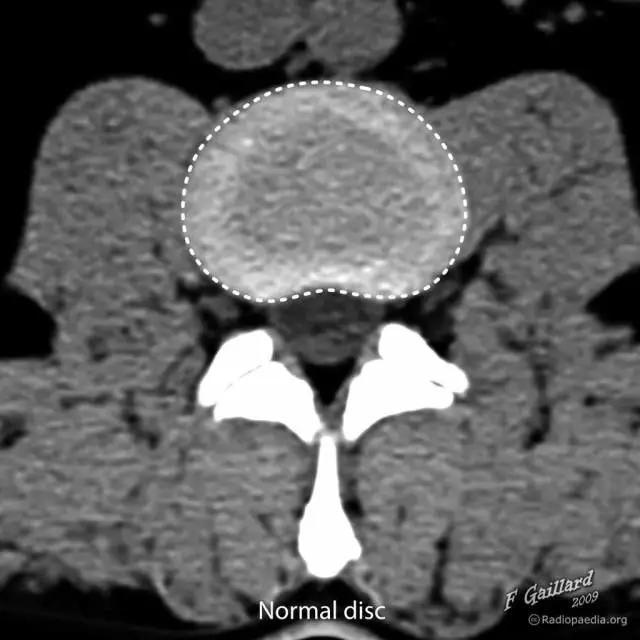

图 1 正常椎间盘示意图,椎间盘由周围的纤维环和中心的髓核组成

图 2 正常椎间盘在相邻两个椎体之间,周围不超出椎体的边缘